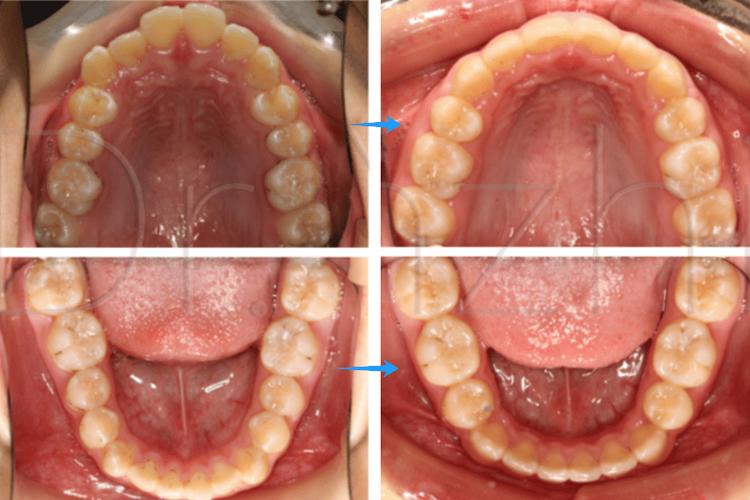

当牙齿拥挤度较大(如拥挤度超过5mm),或牙弓长度明显小于牙齿总宽度时,单纯靠扩大牙弓(如推磨牙向远中)的空间有限,且可能导致牙龈退缩、颊侧黏膜溃疡等问题,此时拔牙(通常拔除第一前磨牙,即“4号牙”)是最有效的解决方案,可利用拔牙后的间隙,将拥挤的牙齿重新排列,恢复正常的牙弓形态和邻接关系。

成人前突患者常表现为上唇前翘、微笑时露牙龈,甚至影响闭唇,矫正时需通过拔牙回收前牙,减少牙弓总长度,使嘴唇与牙齿的关系协调,研究表明,对于中重度前突(上切牙唇倾度超过105°),拔牙矫正后患者的侧貌美观度和自信心提升更显著。

如深覆合(上牙覆盖下牙过多)、深覆盖(上牙切端超出下牙切端过多)、锁颌(上牙与下牙无法正常咬合)等问题,可能需要拔牙调整牙弓的倾斜度和位置,拔除上下颌对称的前磨牙,可通过内收前牙、压低后牙,改善咬合接触点和咀嚼功能。